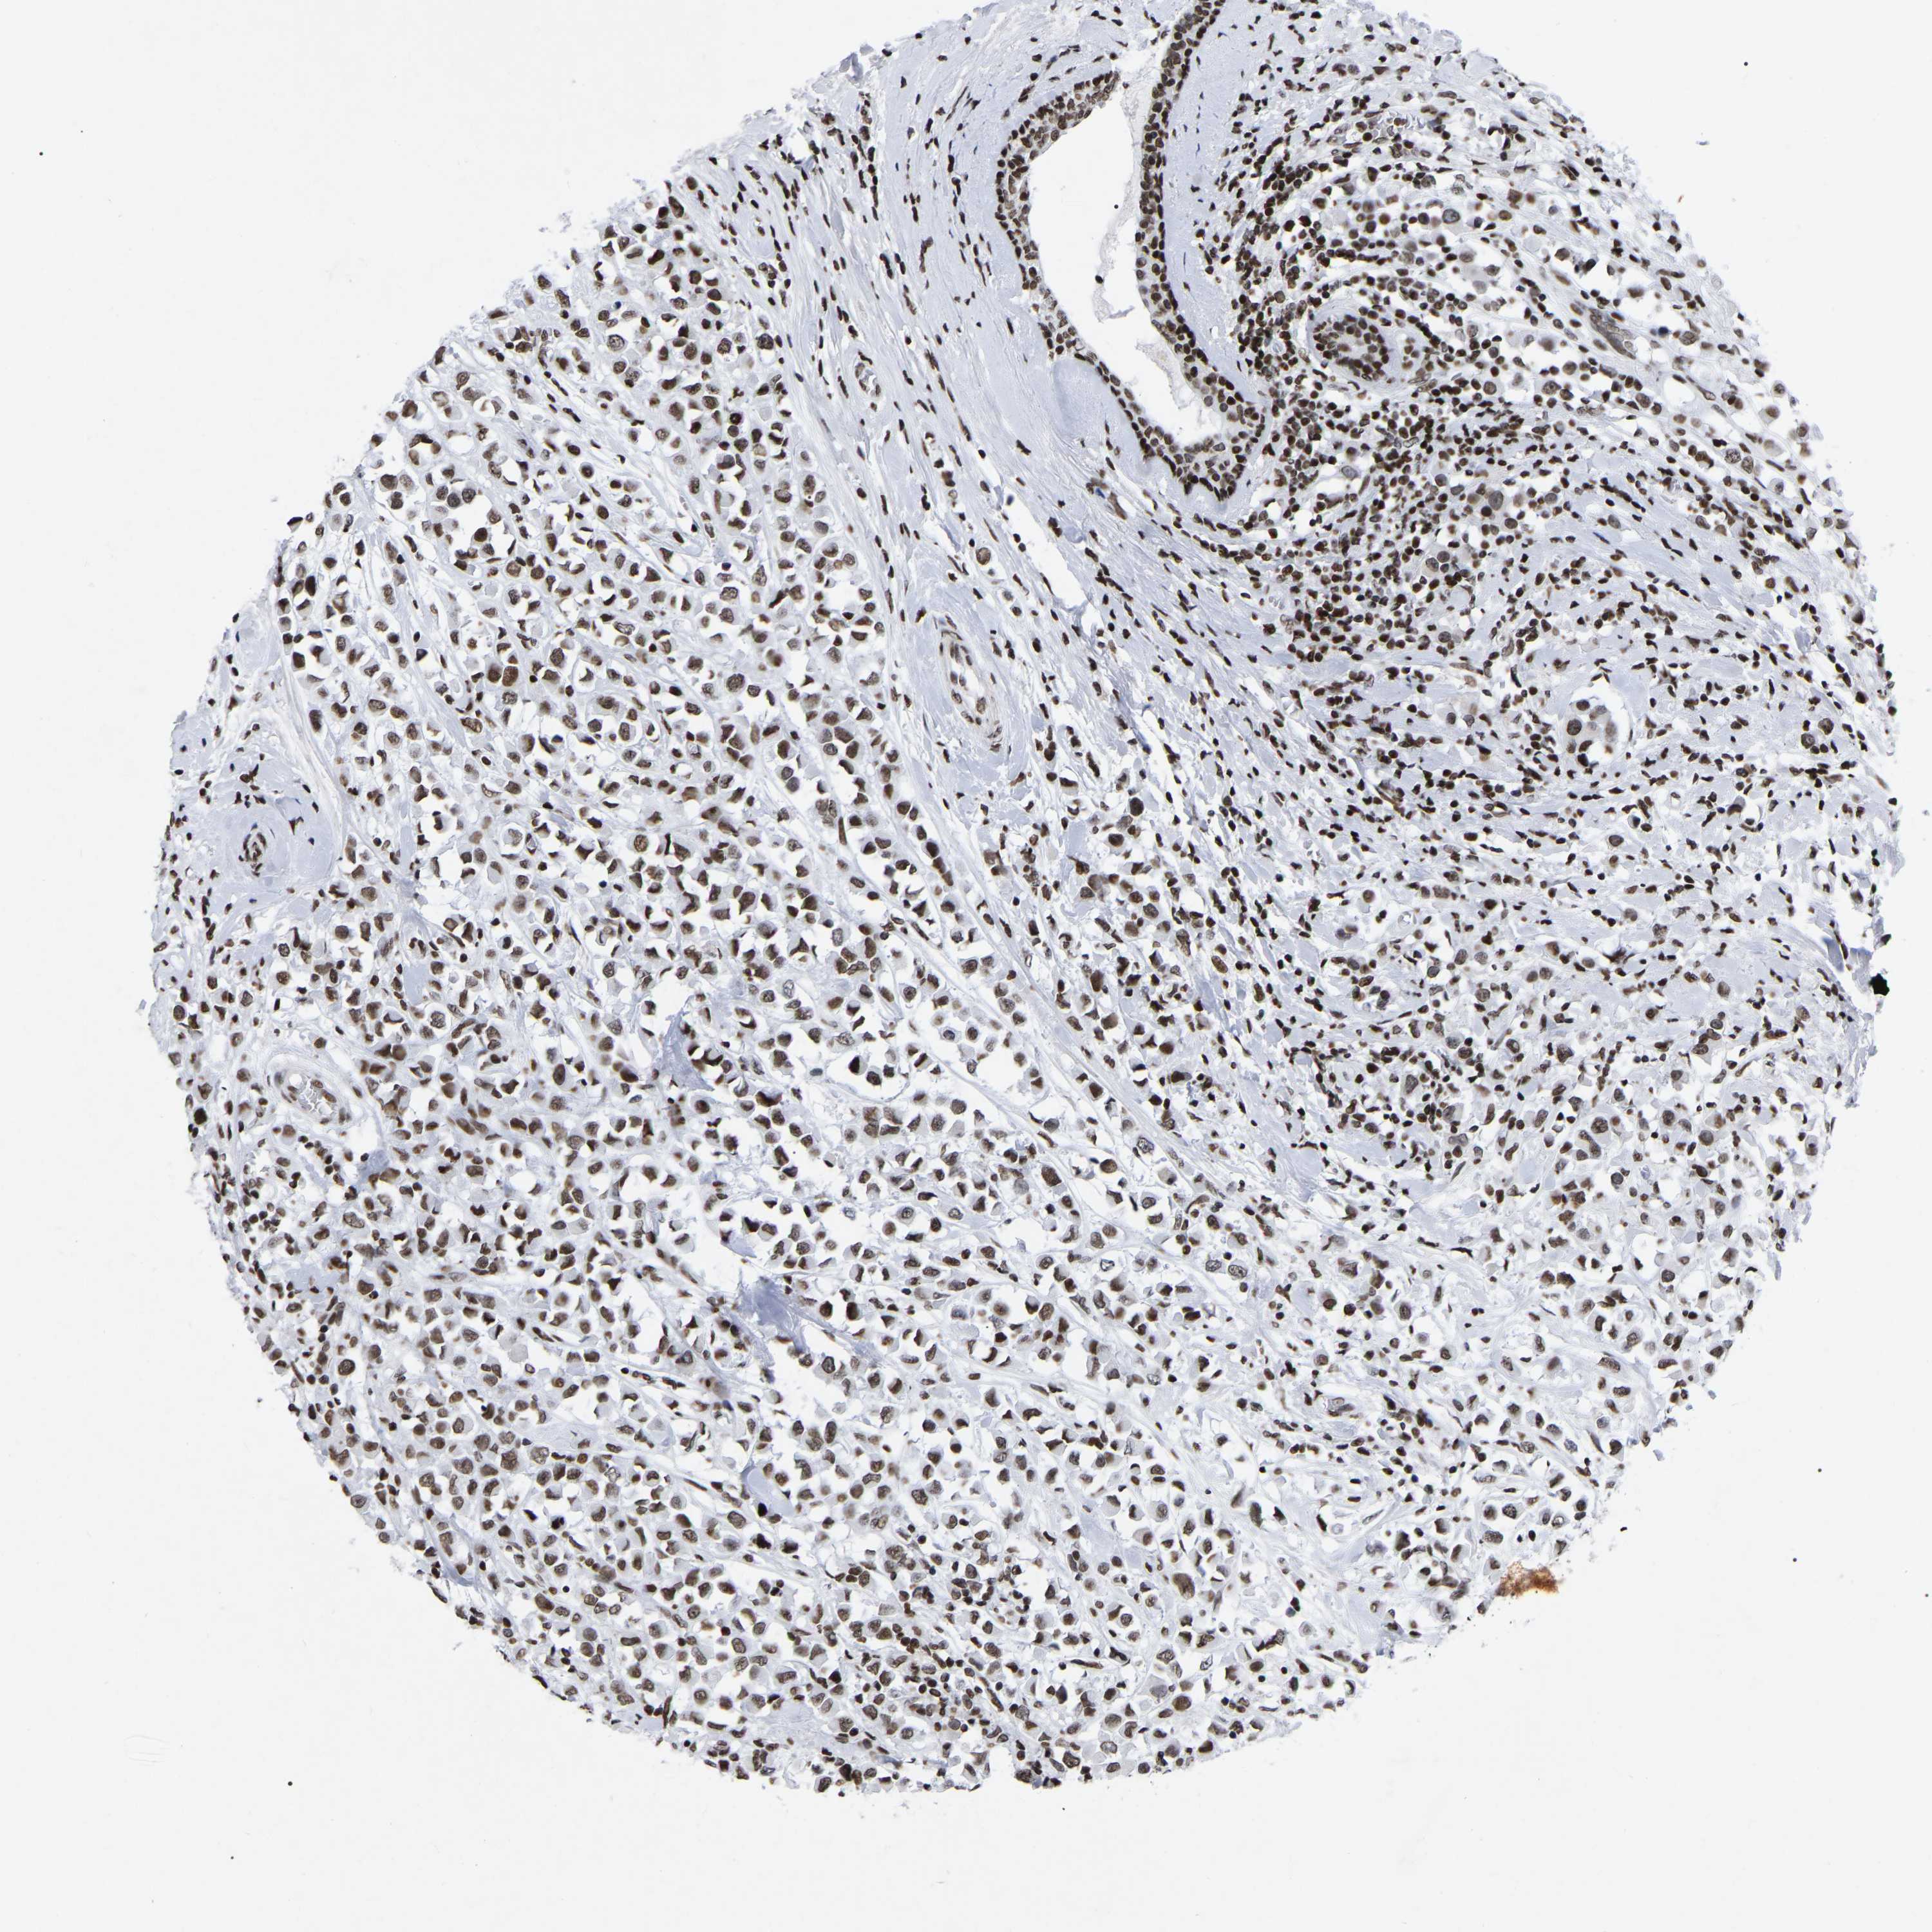

CANCER BREAST CANCER Show tissue menu

BRCA TCGA BRCA VALIDATION PROTEIN EXPRESSION